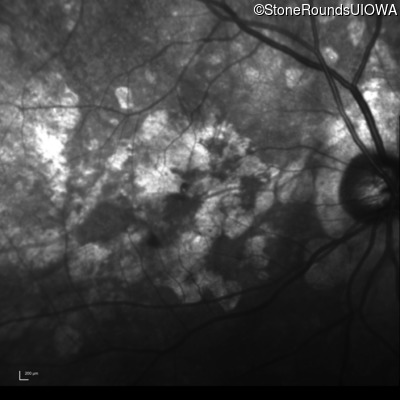

Age at visit: 64 years

This 64 year old woman first noticed some distortion in her vision at age 46 while looking at graph paper.